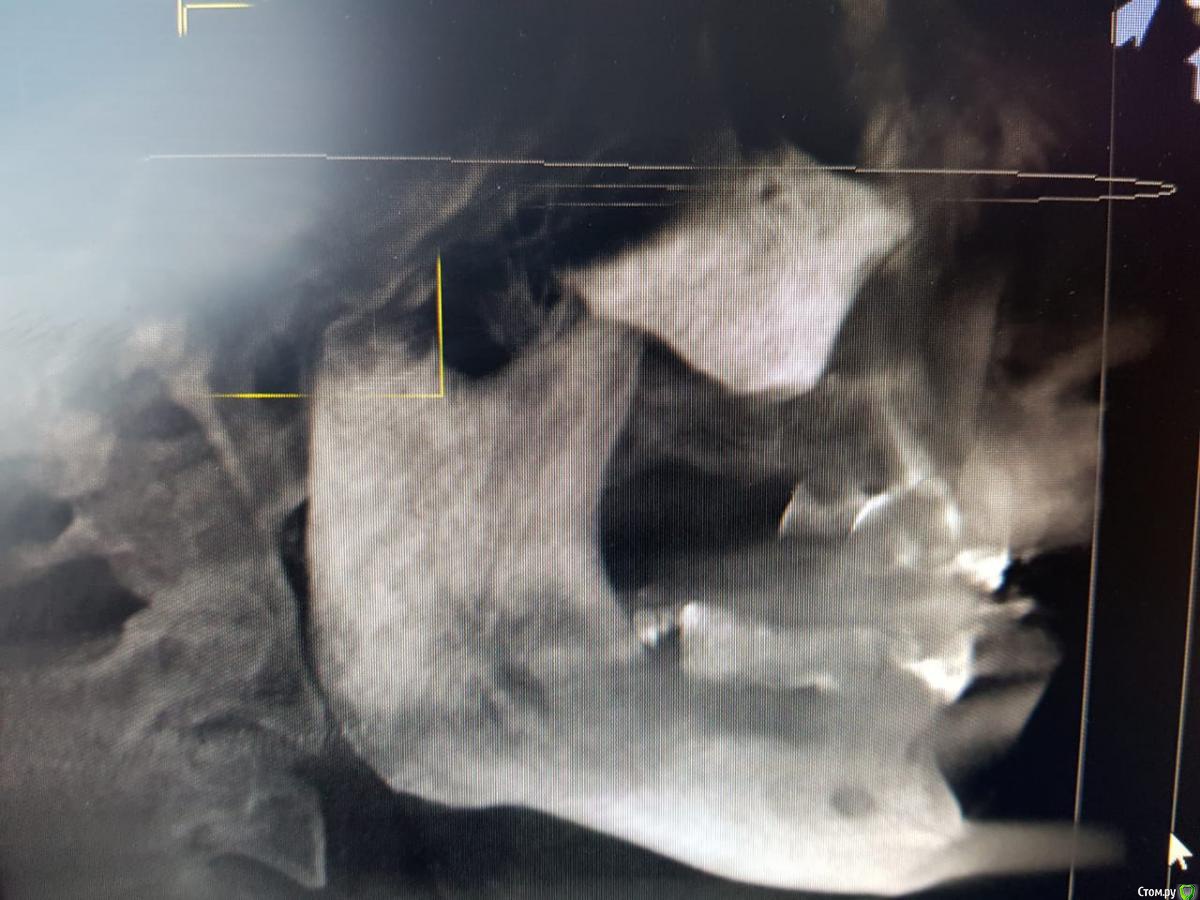

Sunshine Опубликовано 14 марта, 2019 Поделиться Опубликовано 14 марта, 2019 Уважаемые, врачи!Моему отцу 2,5 года назад установили импланты (в другом регионе), и сделали мост, "зацепившись" за живой зуб и имплант...Его ничего не беспокоило до недавнего времени. Теперь вся эта конструкция начала ходить ходуном ... приносит ему боль, естественно полноценно кушать не может.Обратившись в стоматологию по новому месту жительства, стоматологи сообщили, что так делать нельзя ни при каких обстоятельствах, и что надо все снимать, оставшиеся зубы удалять, ждать пока рассосется образовавшаяся киста в районе существующего импланта, и устанавливать новые импланты. Соответственно, вопрос. Так как отец в пенсионном возрасте, то крайне боится вообще остаться без зубов, для него это трагедия. Какие существуют варианты развития событий в нашей ситуации в "щадящем" режиме, но чтобы было все грамотно и четко сделано, дабы больше не возвращаться к вопросу зубов на верхнем ряду. p.s врач который устанавливал данную конструкцию сказал чтоб приезжали-он все поправит, но я его уже не отпускаю, потому что думаю это снова на пару лет...а дальше только хуже... Ссылка на комментарий

kramer Опубликовано 14 марта, 2019 Поделиться Опубликовано 14 марта, 2019 а что возможно сделать, не прибегая к удалению оставшихся зубов? Имеет ли смысл оставлять их? Какие последствия? Зубы верхней челюсти несостоятельны, сохранить нельзя Если на время удаления всей конструкции ставить съемный протез(это я так понимаю снимаются на ночь и в стаканчик? )), то это же только на то время пока не приживутся новые имплантаты? (примерно 3-6 месяцев) Временный протез несъемный, прикручивается в день операции или через несколько дней (при условии, что первичная стабильность имплантатов хорошая. Если нет, тогда как по сценарию, который вы написали) и что с кистой? Удаляется вместе с имплантатом Ссылка на комментарий

Sunshine Опубликовано 14 марта, 2019 Автор Поделиться Опубликовано 14 марта, 2019 А подскажите, пожалуйста, еще вот такой момент.Если недостаточно костной ткани, что я уже успела понять на верхней челюсти не редкость, то еще необходимо наращивание костной ткани?Или есть системы, которые помогают обойтись без этой процедуры? читаю про одного швейцарского производителя(не знаю можно ли приводить название производителей), и приведу цитату: "увеличивает скорость образования костной ткани" . Т.е. костная ткань сама восстанавливается? Ссылка на комментарий